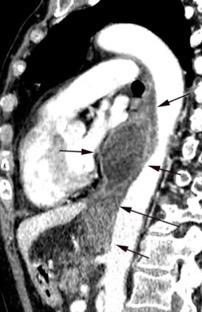

Diafragma “colgante” (“dangling sign”)

(“Dangling sign”)

TC. Mejor con multicorte. (reconstrucciones).

Asociación: Aire en pared.

Fracturas costal .Rotura esplénica. Neumoperitoneo.

Diafragma discontinúo Herniación de la grasa omental

Desser TS et al.The dangling diaphragm sign: sensitivity and comparison with existing CT signs of blunt traumatic diaphragmatic rupture. Emerg Radiol 2010